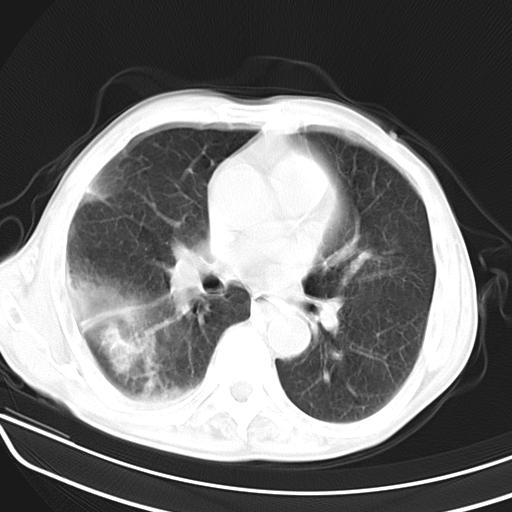

抗炎治疗10天后复查

抗炎治疗10天后复查:右上肺模糊阴影明显减少。